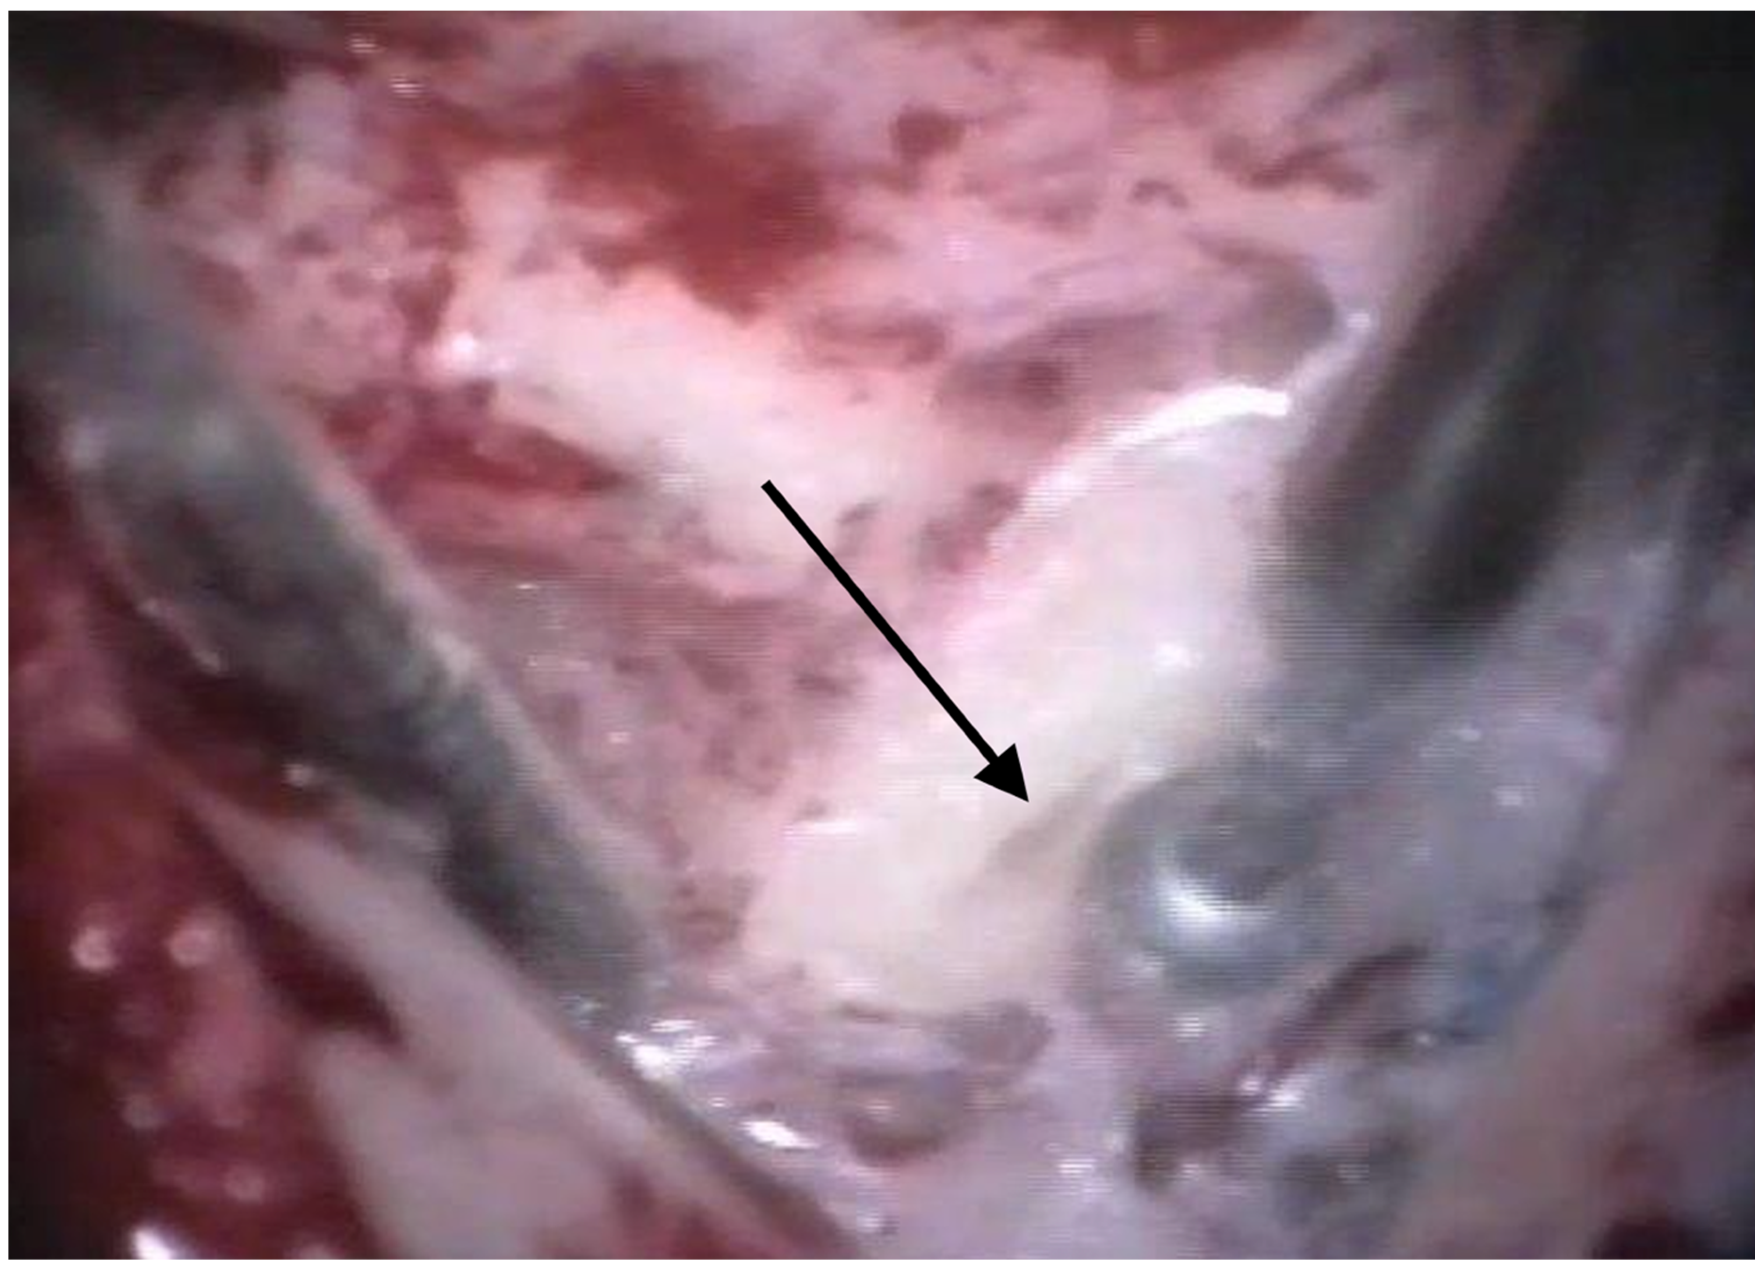

The patients were treated between August 2013 and October 2015 using the identical surgical technique of one-stage cochlear implantation and the occlusion of all three ipsilateral semi-circular canals. For cochlear implantation, a posterior tympanotomy and a round window approach were chosen [14]. Occlusion of the three semi-circular canals was performed before the implantation by reducing the drill speed to 10,000/min. The labyrinth was skeletonized to identify all semi-circular canals. The superior bony layer of the semi-circular canal was drilled down with a diamond burr (2.3 mm) until the endolymphatic duct shone through the last bony layer (blue lining) (Figure 1 and Figure 2). Leaving the endolymphatic duct intact, the temporalis fascia was pushed down in the canal. After sealing with fascia, the canal was filled with bone wax (Figure 3). The area of each canal was covered afterward with a muscle patch and bone pate. Finally, the sealing patch was secured with fibrin glue (Figure 4) [5,15].

Figure 2. After blue lining of the lateral semi-circular canal, the canal was filled with fascia. The arrow points to the lateral semi-circular canal.